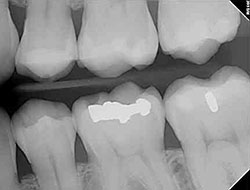

Digital X-Rays

x-rayUsing the most advanced dental technology possible is just as important as staying up-to-date on the latest treatment techniques. Because our practice is dedicated to providing you with the safest and most convenient treatment options available, we utilize advanced digital X-ray technology in our office.

Digital X-rays provide several advanced imaging options that are designed to save time, provide clearer dental photos, and expose patients to less radiation than with traditional X-ray technology.

Our practice is focused on making your dental experience as comfortable as possible. At your next appointment, we’ll be happy to answer any questions you may have.